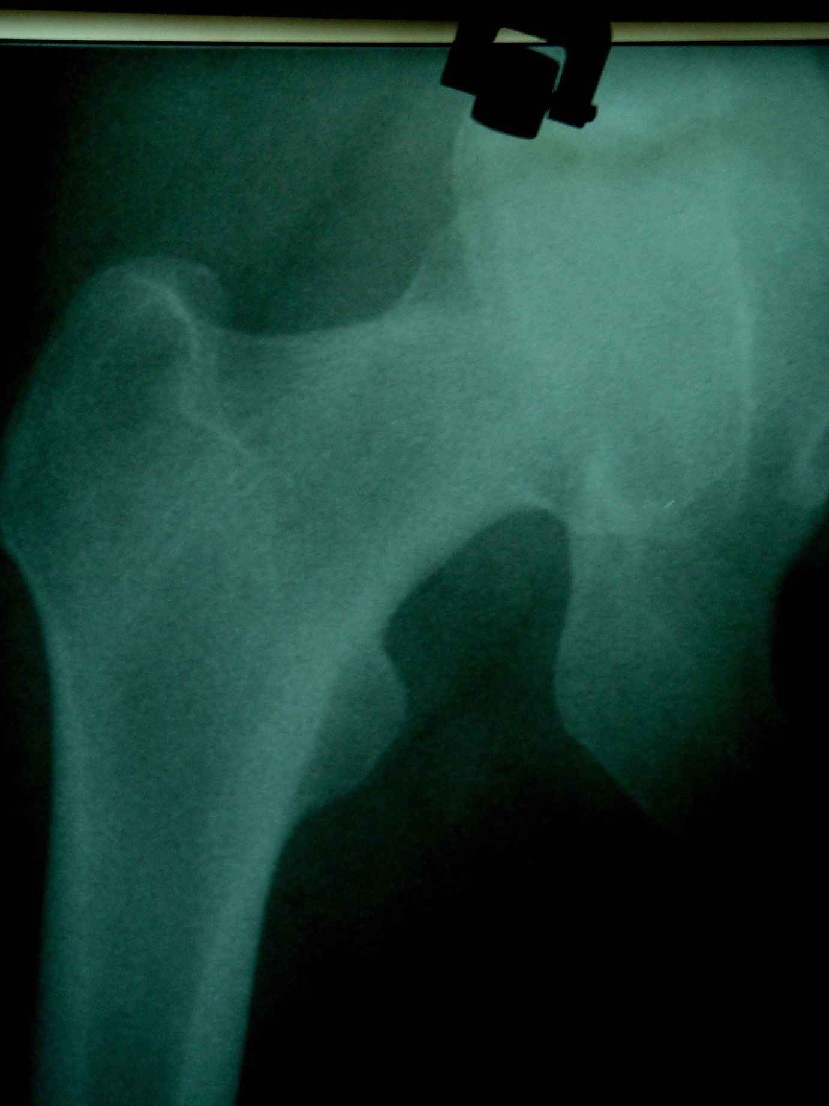

患者,女,因外伤就诊。摄骨盆及右股骨。当时报告骨盆未见明显异常,右股骨中段粉碎性骨折。五天后行股骨中段骨折内固定手术,术中摄床边片示股骨颈骨折。现把术前和术中图像上传。请大家高诊,分析股骨颈骨折是术前漏诊还是其他原因。术前骨盆片右股骨颈显示欠佳是由于股骨中段骨折无法将股骨颈完全显示。

这里还有几张该患者的几张x 光片。

现在我向大家请教,股骨中段粉碎性骨折的同时股骨颈也会骨折吗,另外如图所示该患者股骨颈骨折线是我们常见的由外伤引起的骨折线吗。

回头看术前片,可见一低密透光区.

楼主给我们大家提供了非常好的片子,感谢!该片股骨颈的骨折术前看不到骨折。这个和体位也有关,但是我们都知道,那些标准的体位是给健康人设计的,外伤比较重的往往都无法标准投照。不知道同行们有没有这样一种感受:发现明显的问题了,就心里比较踏实了,舒坦了,就不容易对其它细节仔细观察了。如果没有发现明显的问题,就仔细的翻来覆去的看。所以这个片子给我们很大的教训:仔细阅片!即便是已经发现问题了。如果非要给鸡蛋里面挑骨头,我认为楼主忽略了右髋关节囊的肿胀,诊断报告应该提一下。外伤的病人我最怕股骨颈的漏诊,一般我都要看软组织。我是一个小医院的,我深有感触,发现骨折不是功劳,而漏诊却是事故,还遭受别人耻笑:放射科的连骨头断没断都看不出来!

关于楼主说的骨折线的形态,的确和一般外伤的有种不太一样的感觉,上方裂隙较明显,下方骨皮质“连续”,我认为成年人应该是全部断了的,不全骨折的可能性非常非常小,该片恰好无法全部显示骨折线。骨折线的形态不能判定术前还是术后骨折。以上只是个人小小看法,请各位老师指正为谢!